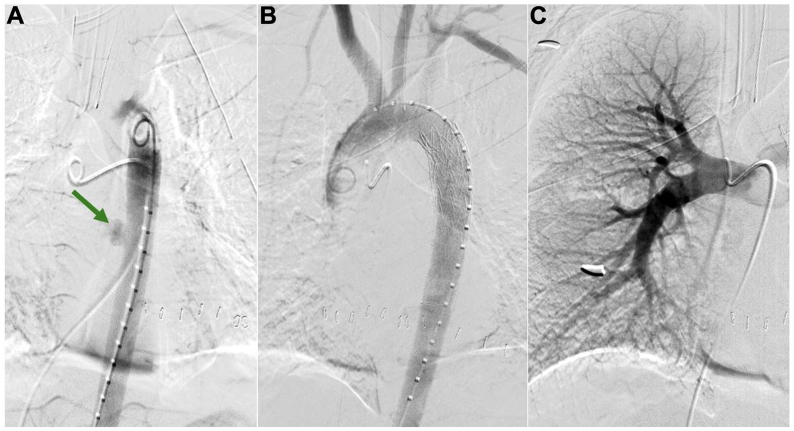

A 17-year-old boy presented after sustaining gunshot wounds to the right chest and upper extremity. Prior to hospital arrival, the patient was hypotensive (systolic blood pressure approximately 70 mm Hg), underwent bilateral chest needle decompression, and received one push of epinephrine by paramedics. Upon transfer to the trauma bay bed, the patient went into pulseless electrical activity arrest. A resuscitative thoracotomy with simultaneous right tube thoracostomy was performed with return of 950 mL of blood. At the same time, a massive transfusion protocol was activated using rapid infusion. Upon entry into the left chest, a periaortic hematoma was visualized, suspicious for thoracic aortic injury. Return of spontaneous circulation was achieved with cardiac massage and rapid transfusion. Systolic pressures improved to >160 mm Hg. With the extent of vascular injury unknown and the patient stabilizing, a computed tomography arteriogram (CTA) of the chest, abdomen, and pelvis was performed, revealing TAI of the midthoracic descending aorta with active extravasation into the mediastinum and in the region of the right lung hilum (Fig 1). Ballistic fragments were identified in the right lung middle lobe and right groin; however, it was unclear if the bullet was intravascular given evidence of distal perfusion.

Fig 1.

Initial computed tomography angiogram of the chest demonstrated a penetrating thoracic aortic injury with active extravasation into the mediastinum (A) as well as multiple foci of active extravasation within the right lung hilum that could not be localized (B). Areas of extravasation are identified with green arrows.